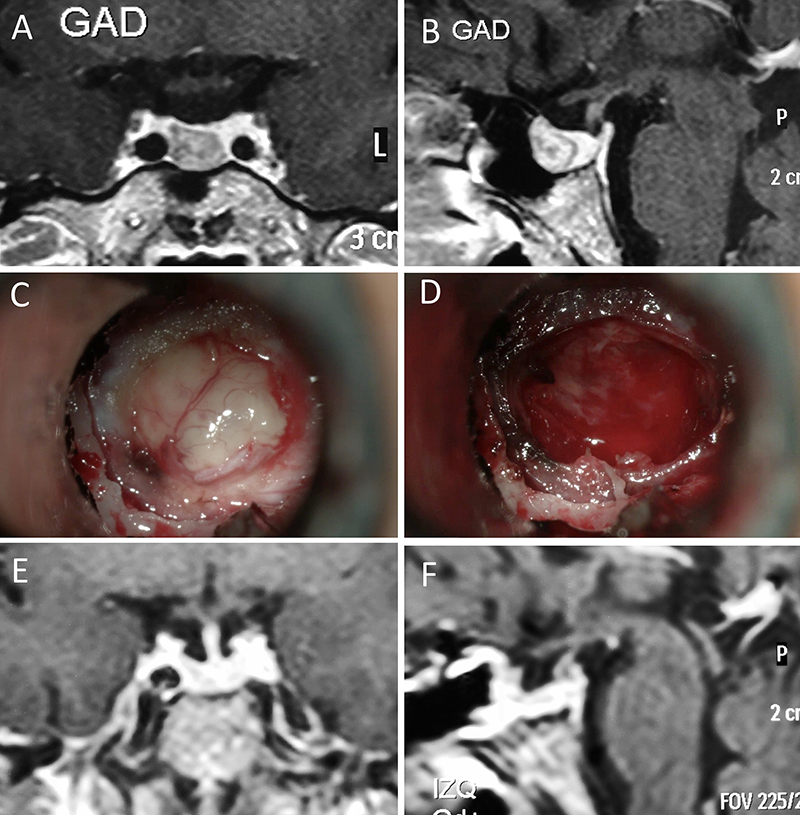

Presentamos 15 casos ilustrativos que consideramos representativos de nuestra serie: 4 enfermos con macroadenomas no funcionantes (figs. 1 a 4); 2 pacientes con macroadenomas con apoplejía (figs. 5 y 6); 4 enfermos con acromegalia (figs. 7 a 10); 3 pacientes con enfermedad de Cushing (figs. 11 a 13) y 2 enfermos con prolactinomas (figs. 14 y 15). El detalle de la presentación clínica de cada paciente y su correspondiente evolución postoperatoria se detalla en el epígrafe de cada ilustración.

Figura 11: Microadenoma en una mujer de 36 años con Enfermedad de Cushing. Con remisión bioquímica tras la cirugía. A-B: RM preoperatoria; C-D: intraoperatorio; E-F: RM postoperatoria.

Figura 12: Microadenoma en una mujer de 26 años con Enfermedad de Cushing. Con remisión bioquímica tras la cirugía. A-B: RM preoperatoria; C-D: intraoperatorio; E-F: RM postoperatoria.